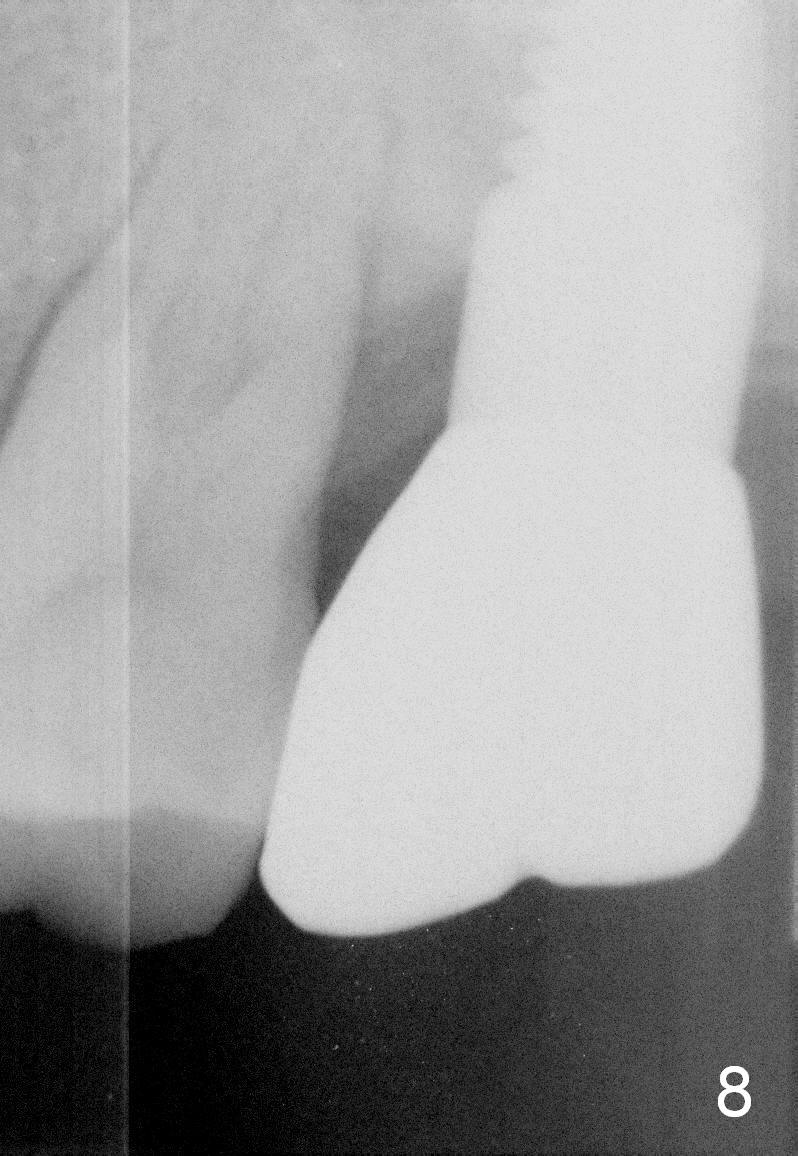

A 50-year-old lady presented to clinic with chief complaint of a loose tooth upper left.  The tooth #15 has complex endo-perio disease (Fig.1,2).  It was extracted on November 29, 2012.  She returned to clinic for implant placement on January 28, 2013.  Under local anesthesia, osteotomy was prepared with combination of bone expansion and drilling (Fig.3: 4x14 tapered drill).  She was not comfortable with tapping.  Finally, Tatum tapered implant (6x14) was placed (Fig.4) with 35 Ncm.  She felt dizzy when she stood up from dental chair. She felt better by the evening of January 29, 2013.  But the following morning, she did not feel good.  She wonders when the symptom will disappears.